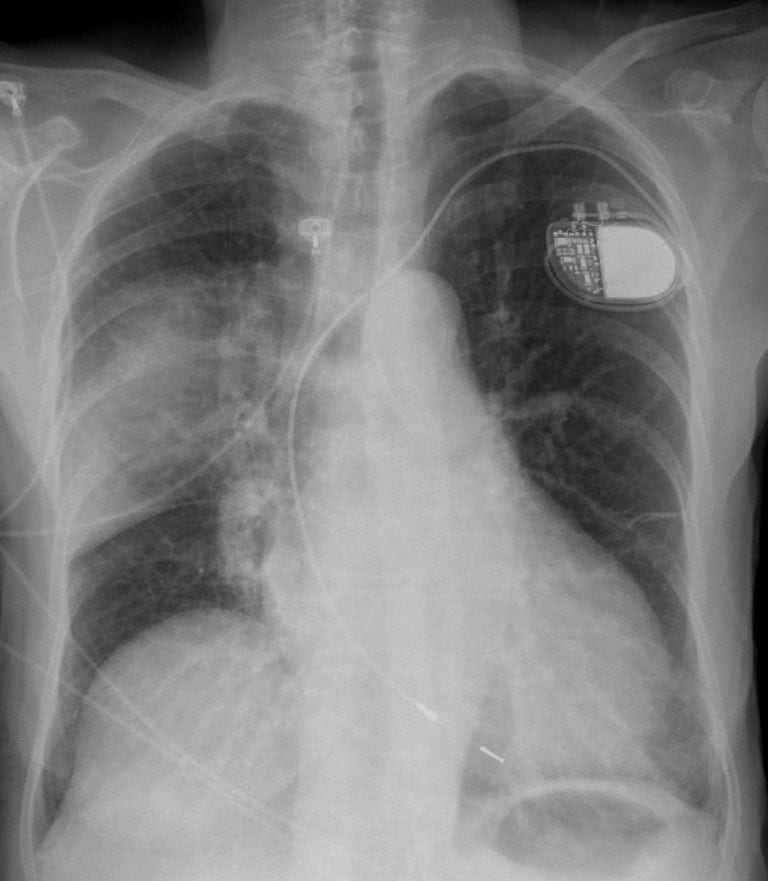

Chest X-Ray Reveals:

CXR Case 118 • LITFL • Chest X-ray Self-Assessment Quiz

- Provide your suspected diagnosis based on the history, outline the physical examination you would perform, list the investigations you would consider, and suggest a potential management plan. Please also indicate your findings from the chest X-ray in the investigations box